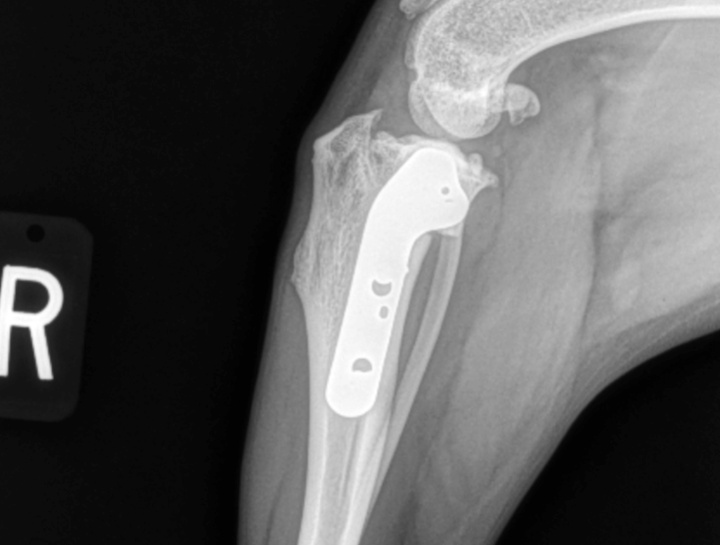

Digital x-rays assist in diagnosing illness & injury.

Digital radiology allows us to better diagnose and treat sick and injured pets by providing us with high-quality imaging results and reducing overall radiation exposure. They can capture digital images of both the body and teeth.